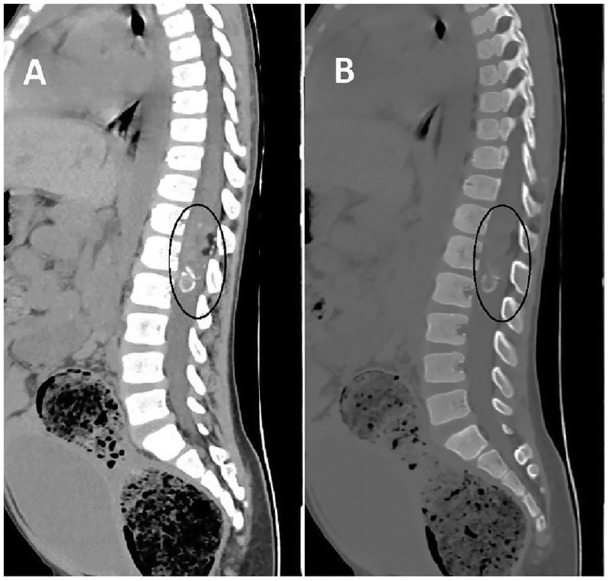

脊柱畸胎瘤虽然在脊柱肿瘤中很少见,但在硬膜内-髓内病变的鉴别诊断中应予以考虑,特别是在出现泌尿和粪便症状的儿童中。全面的影像学评估,包括CT和MRI的特征性发现,如囊性和实性成分,脂肪组织的存在,以及相关的脊髓异常,如鼻咽形成,可以帮助早期诊断。手术切除仍然是治疗的主要方法,及时干预对于预防进展和减轻患者的症状至关重要。在这里,我们讨论一个病例硬膜内-髓内畸胎瘤在一个6岁的儿童谁是及时诊断通过CT和MRI和治疗全手术切除。

Spinal teratomas, though rare among spinal tumors, should be considered in the differential diagnosis of intradural-intramedullary lesions, especially in children presenting with urinary and fecal symptoms. Comprehensive imaging evaluation, including CT and MRI with characteristic findings such as cystic and solid components, the presence of fatty tissue, and associated spinal cord abnormalities like syrinx formation, can aid in early diagnosis. Surgical resection remains the mainstay of treatment, and prompt intervention is crucial to prevent progression and alleviate symptoms in affected patients. Here, we discuss a case of an intradural-intramedullary teratoma in a 6-year-old child who was timely diagnosed using CT and MRI and treated with total surgical resection.